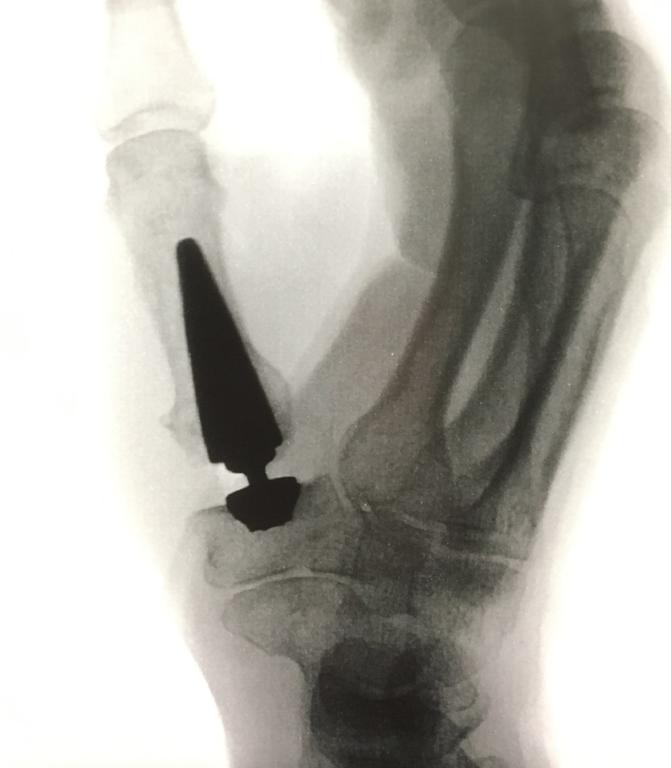

Duimartrose stellen we vast tijdens een klinisch onderzoek. Een radiografie van het duimbasisgewricht bevestigt definitief ons oordeel.

- Bij een duimprothese vervangen we het eigen versleten gewricht door een kunstgewricht. Dit leidt tot een snellere revalidatie met terugkeer van de normale beweeglijkheid en kracht. Net zoals voor overige protheses (bijvoorbeeld heup en knie) geldt ook hier een kleine kans op loslating, ontwrichting of vroegtijdige slijtage. Bekijk de operatievideo.